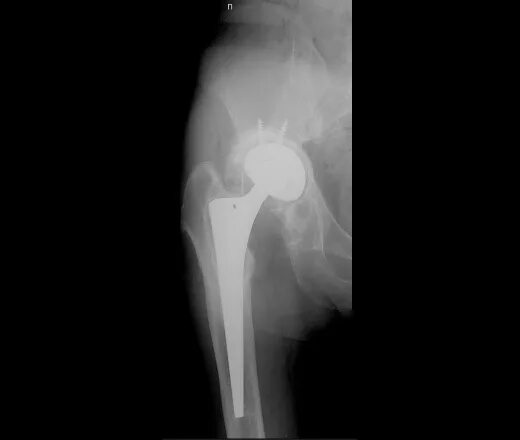

Деформация тазобедренного